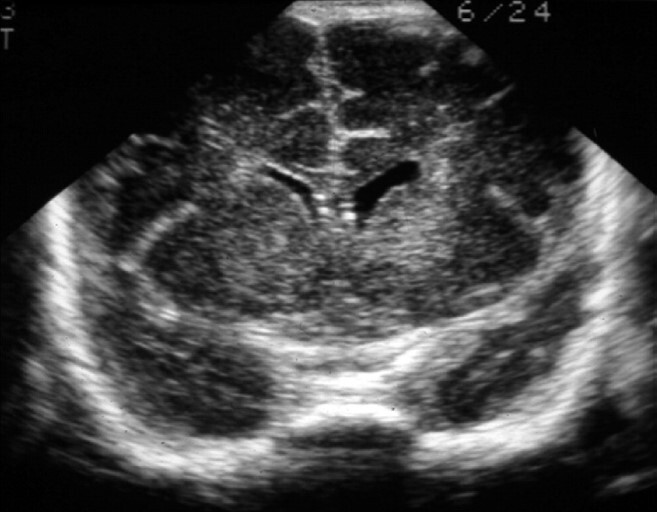

Neonatology Ventricle Asymmetry 1 Image